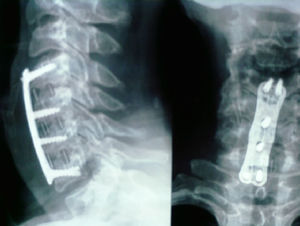

La fusión se consiguió en 18 pacientes (94%) del grupo de cresta ilíaca (fig. 1) y en 12 pacientes (71%) del grupo cajetín de PEEK-aloinjerto (fig. 2). Un paciente del grupo de cresta ilíaca (fig. 3) y 5 pacientes del grupo cajetín-aloinjerto desarrollaron seudoartrosis.